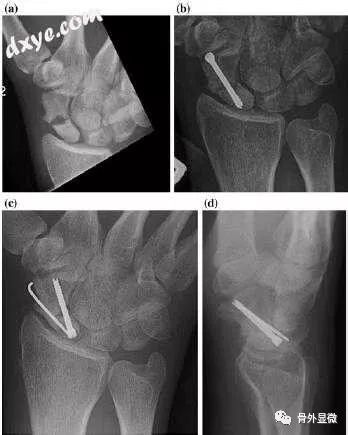

手腕和手的不愈合 骨外显微 微信公众号文章阅读 Wemp